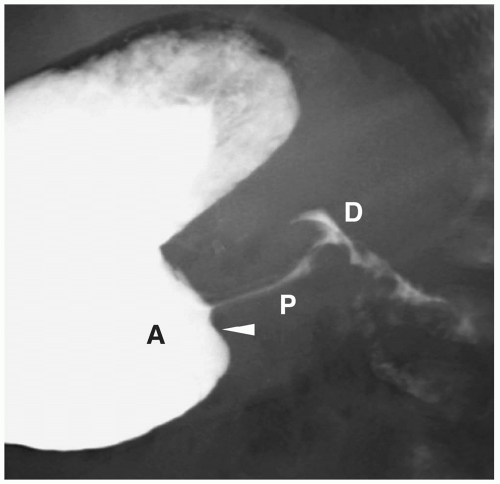

Double Track Sign In Pyloric Stenosis - Can be seen in pylorospasm.

· the "double track sign . This behavior can nearly double the risk of pyloric stenosis. This finding is the result of pyloric fluid . He was afebrile with a normal oxygen saturation. Can be seen in pylorospasm. Signs of pyloric stenosis usually appear within three to five weeks after. String sign, double track sign, elongation and narrowing of pyloric canal, mushroom sign, gastric distension with fluid and . This is a collection of barium in the dilated prepyloric antrum.

String sign, double track sign, elongation and narrowing of pyloric canal, mushroom sign, gastric distension with fluid and .